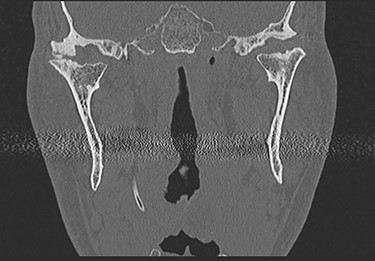

This report is about a 63-year-old patient suffering of bilateral deforming TMJ arthrosis (Wilkes-V) from a bilateral condylar fracture. In 2019 he presented himself to the Department of Oral and Maxillofacial Surgery, showing painful palpation above both TMJs and a severely decreased mouth opening (maximum interincisal distance of 1.5 cm). A computed tomography (CT) scan then revealed pathognomonic changes with flattening of the condyle and articular eminentia as well as partial ankylosis of the right TMJ (Fig. 1). Based on these findings, we decided for a bilateral TMJ-TJR. At this point, the patient only wanted one side replaced for the time being. After impressions were taken, plaster models were 3D-surface scanned and in combination with the CT dataset further processed by Zimmer-BiometTM (Warsaw, USA) for patient-specific TJR (PSI-TJR) fabrication. Another 3 months later, the TMJ-TJR of the right side could be carried out (Fig. 2). Postoperatively the patient received antibiotics for overall 7 days. Satisfied with the result, the patient requested reconstruction of the left TMJ 6 months later. With an improved mouth opening (2.8 cm), impressions were taken using an intraoral scanner. After PSI fabrication, the operation was carried out 9 months after (Fig. 3). Six weeks following surgery, the patient presented with a painful preauricular swelling on the left side, which was diagnosed as aseptic inflammation in the absence of erythema and pathologic joint puncture. Showing a periarticular edema, a broken screw and radial osteolysis around the drilling channels, a subsequent CT scan indicated the loosening of the ultra-high-molecular-weight-polyethylene (UHMWPE) fossa component (Fig. 4). In view of the long production time of new custom-made components and the damaged implant site, we decided to explant the fossa and to temporarily replace it with a non-fixed patient-specific spacer made of COPAL®-bone-cement (Fig. 5) (gentamicin and clindamycin additive) (Haereus; Hanau, Germany). The workflow included the surface scan of the original fossa-drilling template, the computer-aided design of a two-part press mould and the intraoperative fossa fabrication from COPAL®-bone-cement. With the use of a rubber elastic intermaxillary fixation, the vertical mandibular relation could be secured, painful movements and muscle shortening avoided and the risk of perioperative infection could be sufficiently minimized (Fig. 6). After 3 months without complications, the patient-specific COPAL® component could be removed and the new patient-specific UHMWPE fossa inserted within sufficiently regenerated bone (Fig. 7).

Intraoperative image showing the articular fossa (A) in combination with the articulating condylar component (B), the fixed ramus component (C) and the postoperative CBCT of the right side (D).